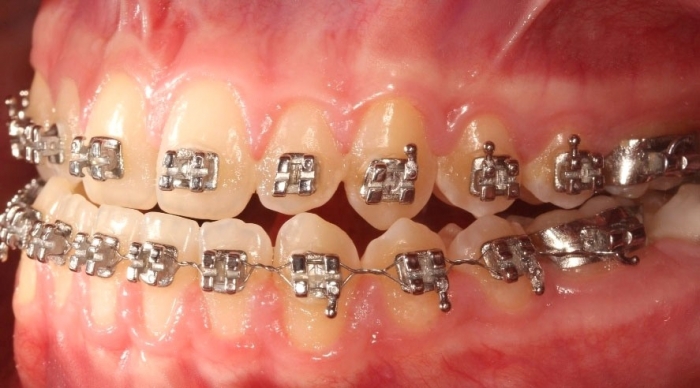

Mordida após a cirurgia realizada em 2016 - Clínica Cliniface

Mordida após a cirurgia realizada em 2016